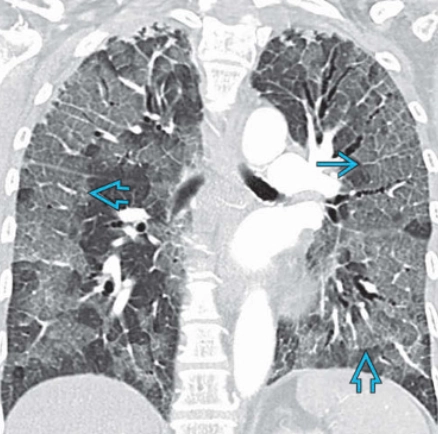

Viêm phổi tăng bạch cầu ái toan cấp tính (Acute Eosinophilic Pneumonia - AEP)